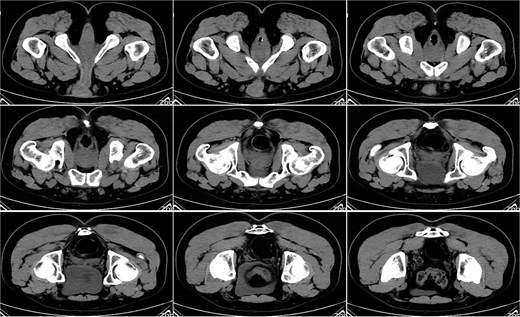

On postoperative Day 10, a repeat complete blood count showed a white blood cell count of 9.74 × 109/l and a neutrophil percentage of 69.5%. The patient’s temperature ranged between 36.4 and 37.4°C, and abdominal discomfort was partially alleviated. A follow-up pelvic CT scan revealed a breach in the anterior rectal wall with gas density shadows communicating with the surrounding area, accompanied by filamentous exudate density shadows and multiple gas density shadows (Fig. 2). These findings indicated rectal wall edema and anterior wall perforation with surrounding infection. Anorectal examination revealed a 0.5 × 0.5 cm ulcerative lesion at the 5 o’clock position of the anastomosis site in the knee–chest position. This was considered rectal perforation secondary to anastomotic dehiscence. Given the absence of peritoneal irritation signs and normalization of the white blood cell count, a conservative treatment plan was adopted after discussion with the patient. This plan involved continuing anti-infective treatment with intravenous cefoperazone sodium and sulbactam sodium.